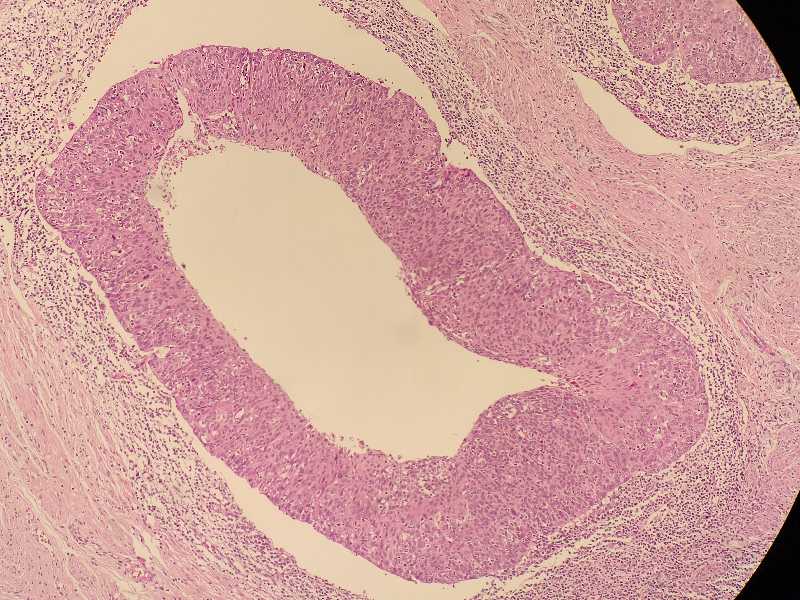

女40岁宫颈锥切组织浸润还是CIN累腺

女40岁宫颈锥切组织 浸润还是CIN累腺?

考虑:鳞癌